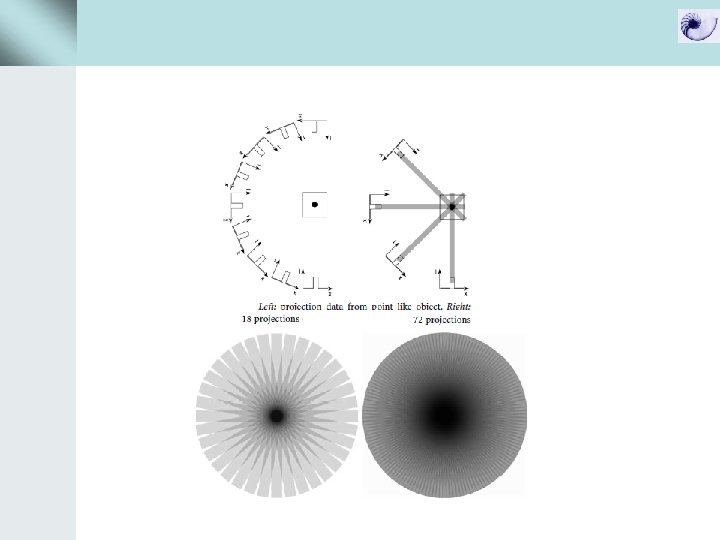

Data acquisition με συμβατικό CT και spiral CT